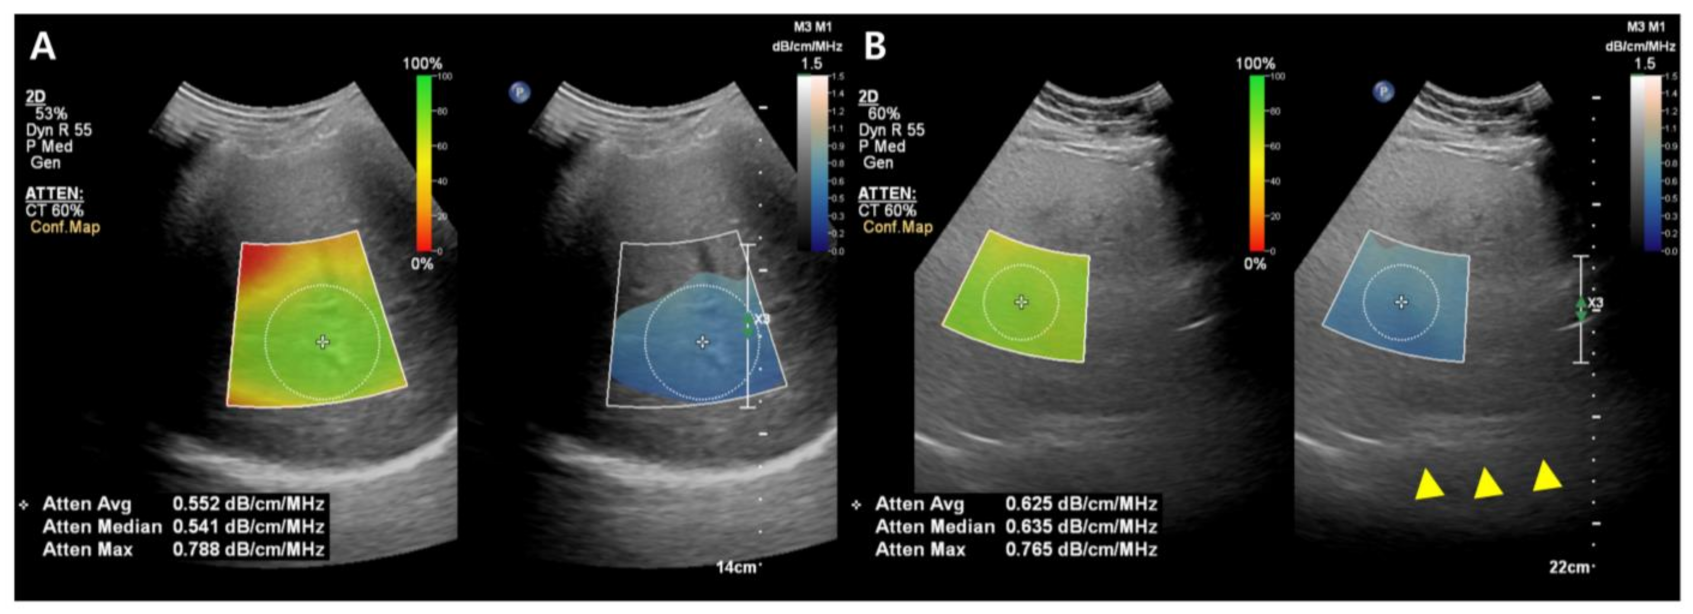

While the details of the evaluation method differ slightly between companies, the typical measurement process is as follows: (1) A convex probe is used to perform a B-mode US evaluation of the liver; (2) the probe is used to visualize the right hepatic lobe via an intercostal window for AC measurement; (3) the region of interest (ROI) is fixed in the right hepatic lobe at least 2 cm below the liver capsule to mitigate reverberation artifacts during breath-hold while excluding large vessels; and (4) the AC value (in dB/cm/MHz) and reliability of the measurement (in R2) are determined (Figure 3). A measurement of R2 ≥ 0.60–0.90 is considered satisfactory, and approximately five satisfactory measurements are used to assess hepatic steatosis. The technical failure rate for these methods, including ATI and UGAP, appears low (0–4.3%), although there is limited data available [36,38,39,40,41,42].

Figure 3.

Images from the attenuation coefficient (AC) from the Philips system (A,B). Mean AC value of image (B) (0.625 dB/cm/MHz) is higher than image (A) (0.552 dB/cm/MHz) which means a larger fat component in the image (B). The echo of the diaphragm is poorly visible (arrowhead). Confidence map is shown as a color box, and the poor-quality areas are not included in the measurement.